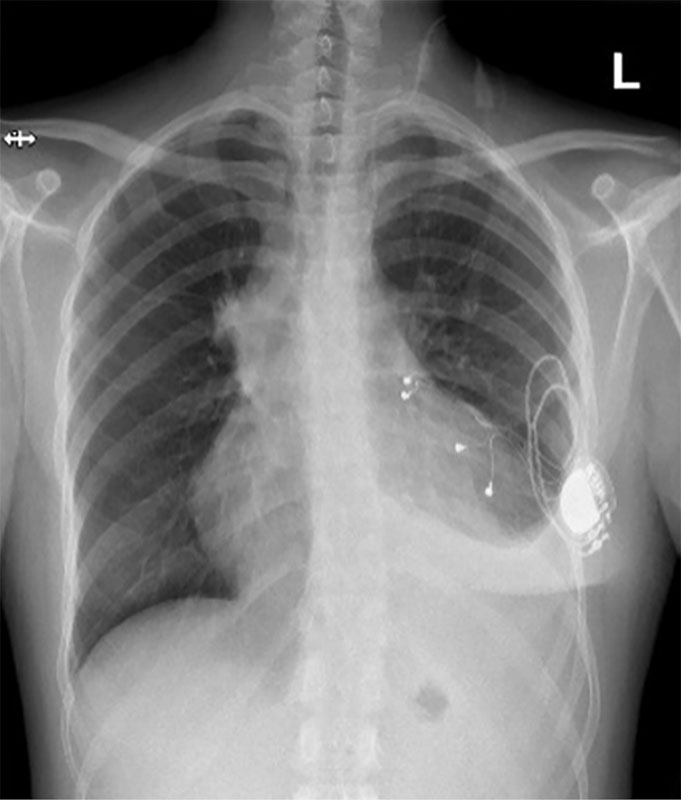

Рис. 2. Рентгенограмма органов грудной клетки, октябрь 2024 г.

Этап 2 – углубленное кардиологическое обследование. 16 октября ХМ-ЭКГ выявило шесть эпизодов наджелудочкового эктопического ритма с АВ-блокадой 2-й степени 2-го типа с максимальной паузой 1932 мс, со средней частотой сердечных сокращений (ЧСС) 59 уд/мин, длительностью около 10 минут, возникших в покое; пароксизм предсердной тахикардии с АВ-блокадой 2-й степени 2-го типа с ЧСС до 51 уд/мин, длительностью 6 с; удлинение корригированного QT-интервала от 450 до 506 мс в течение 15 минут (рис. 1). На ЭхоКГ – признаки тромбоэмболии легочной артерии (ТЭЛА), выраженная легочная гипертензия, значительный гидроперикард, недостаточность трикуспидального клапана 3-й степени и митрального клапана 2-й степени. Снята повторно ЭКГ, показавшая АВ-блокаду 3-й степени. Срочно вызвана бригада скорой медицинской помощи, пациентка госпитализирована в реанимационное отделение городской клинической больницы им. В.В. Вересаева. С целью устойчивого контроля за ЧСС установлен временный электрокардиостимулятор (ЭКС). В результате проведенного обследования диагностирована АВ-блокада 3-й степени. Эквиваленты синдрома Морганьи – Адамса – Стокса (МАС). Установка временного однокамерного нечастотно-адаптивного ЭКС от 17.10.2024 г. (рис. 2).

Медицинские вмешательства. Изначально после госпитализации был установлен временный однокамерный нечастотно-адаптивный ЭКС. Затем, через две недели, выполнена имплантация двухкамерного ЭКС Medtronic Attesta DR MRI SNFNB211604G.